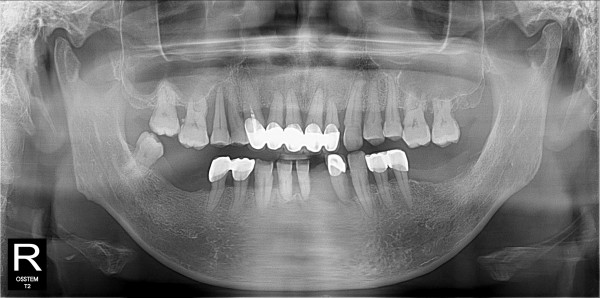

구치부 임플란트 최고관리자 0건 23-11-07 18:32 본문 구치부 임플란트 + 전치부 크라운 목록 이전글구치부 임플란트 23.11.07 다음글구치부 임플란트 23.11.07 댓글목록 0 댓글목록 등록된 댓글이 없습니다.